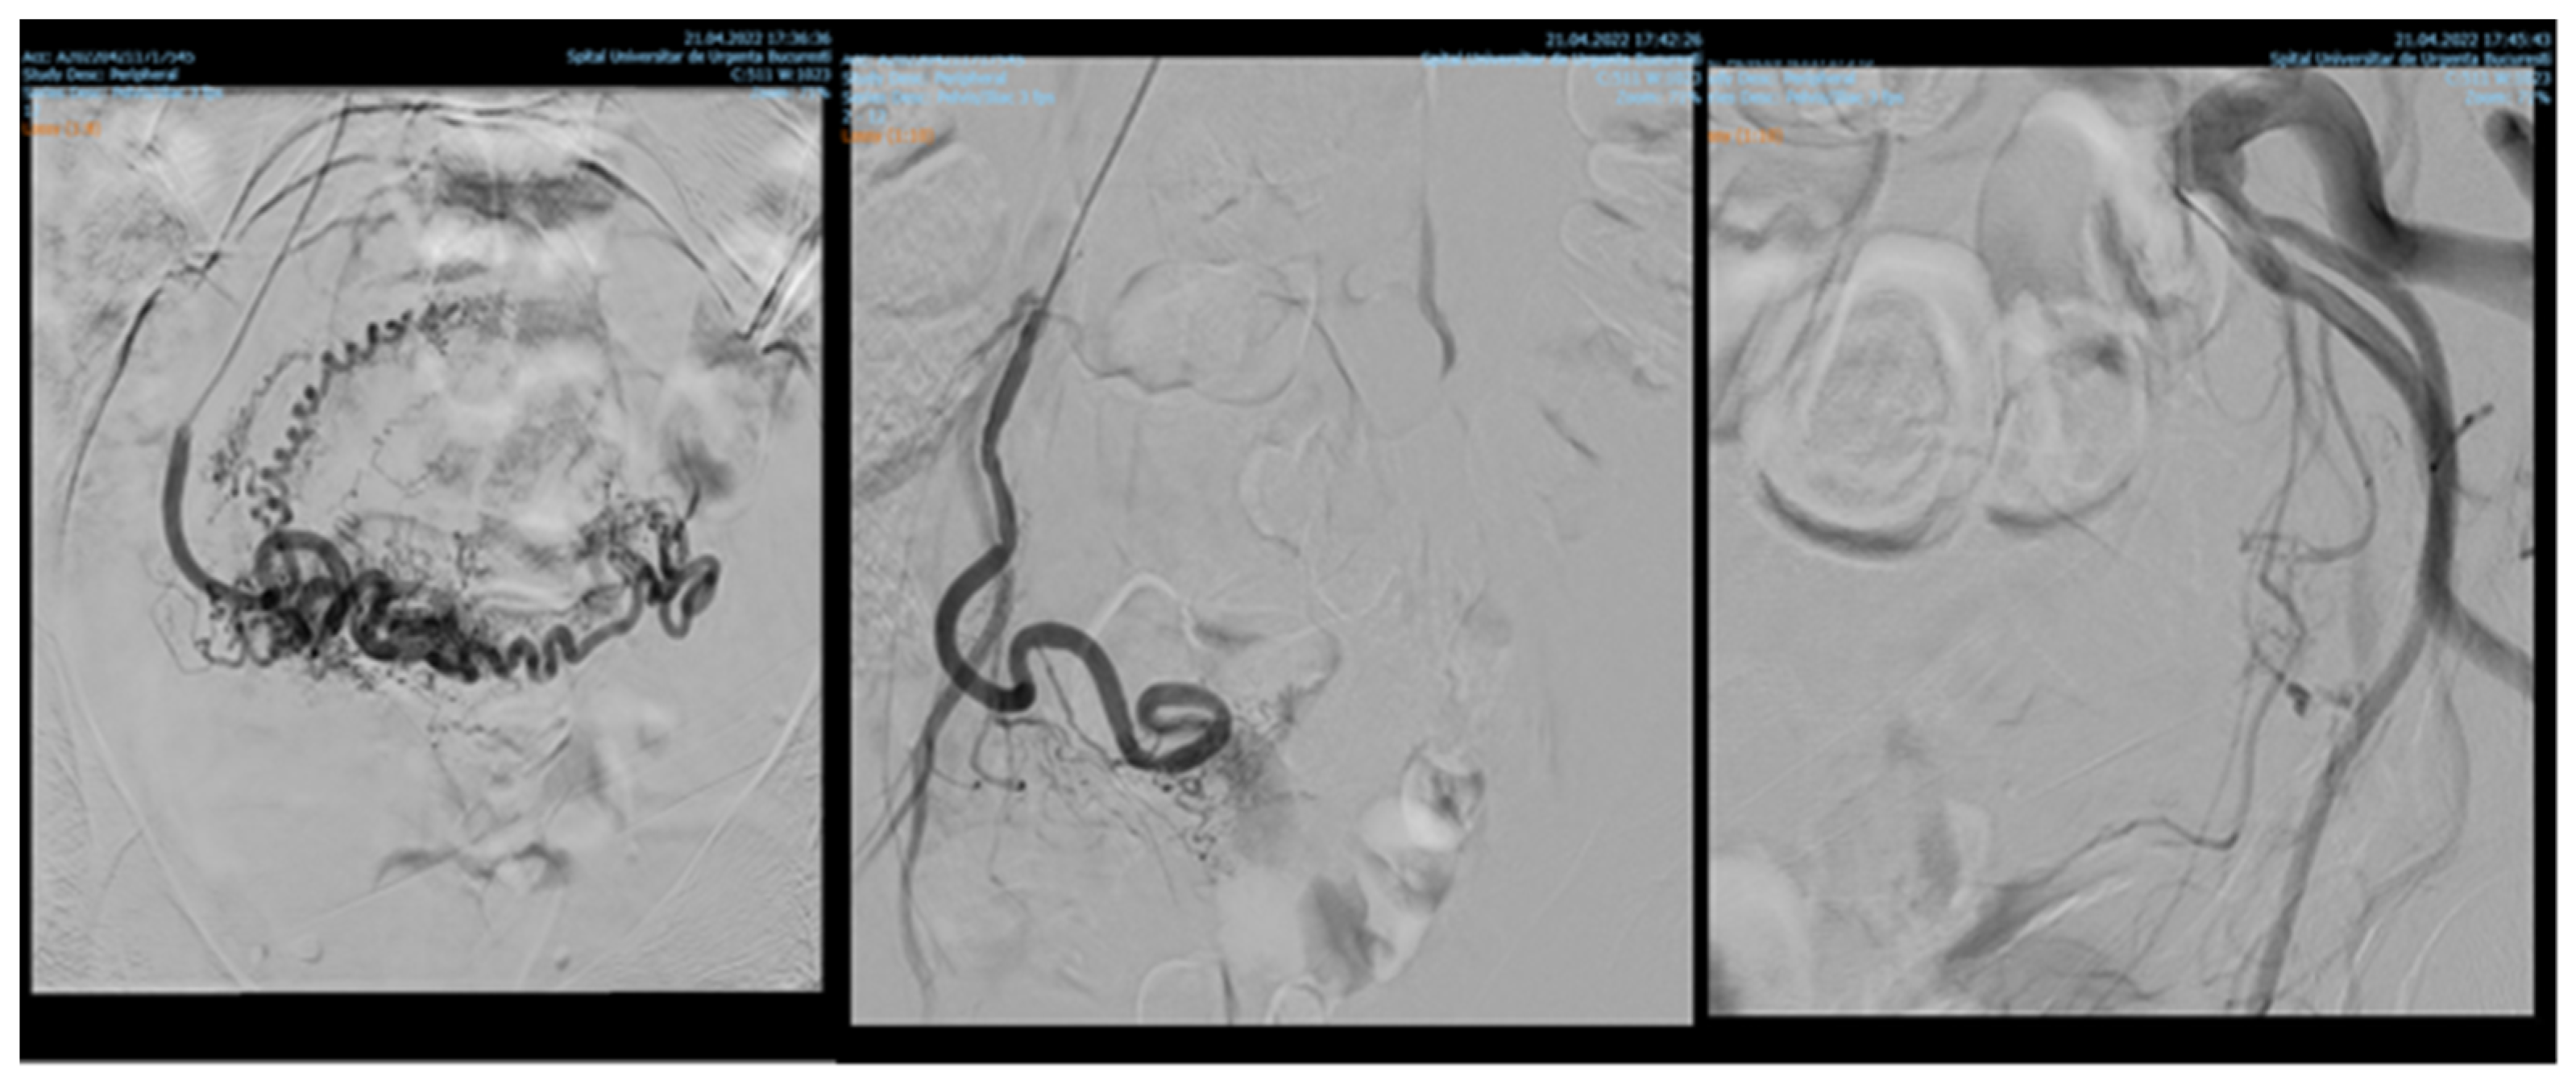

Among 1135 patients, 88.19% presented with uterine leiomyomas (n = 1001), where supra-selective uterine arteries embolization was used. Pre- and postprocedural aspects of uterine artery embolization in a patient with uterine leiomyomas are shown in Figure 1.

Figure 1. Uterine artery embolization in uterine leiomyoma.